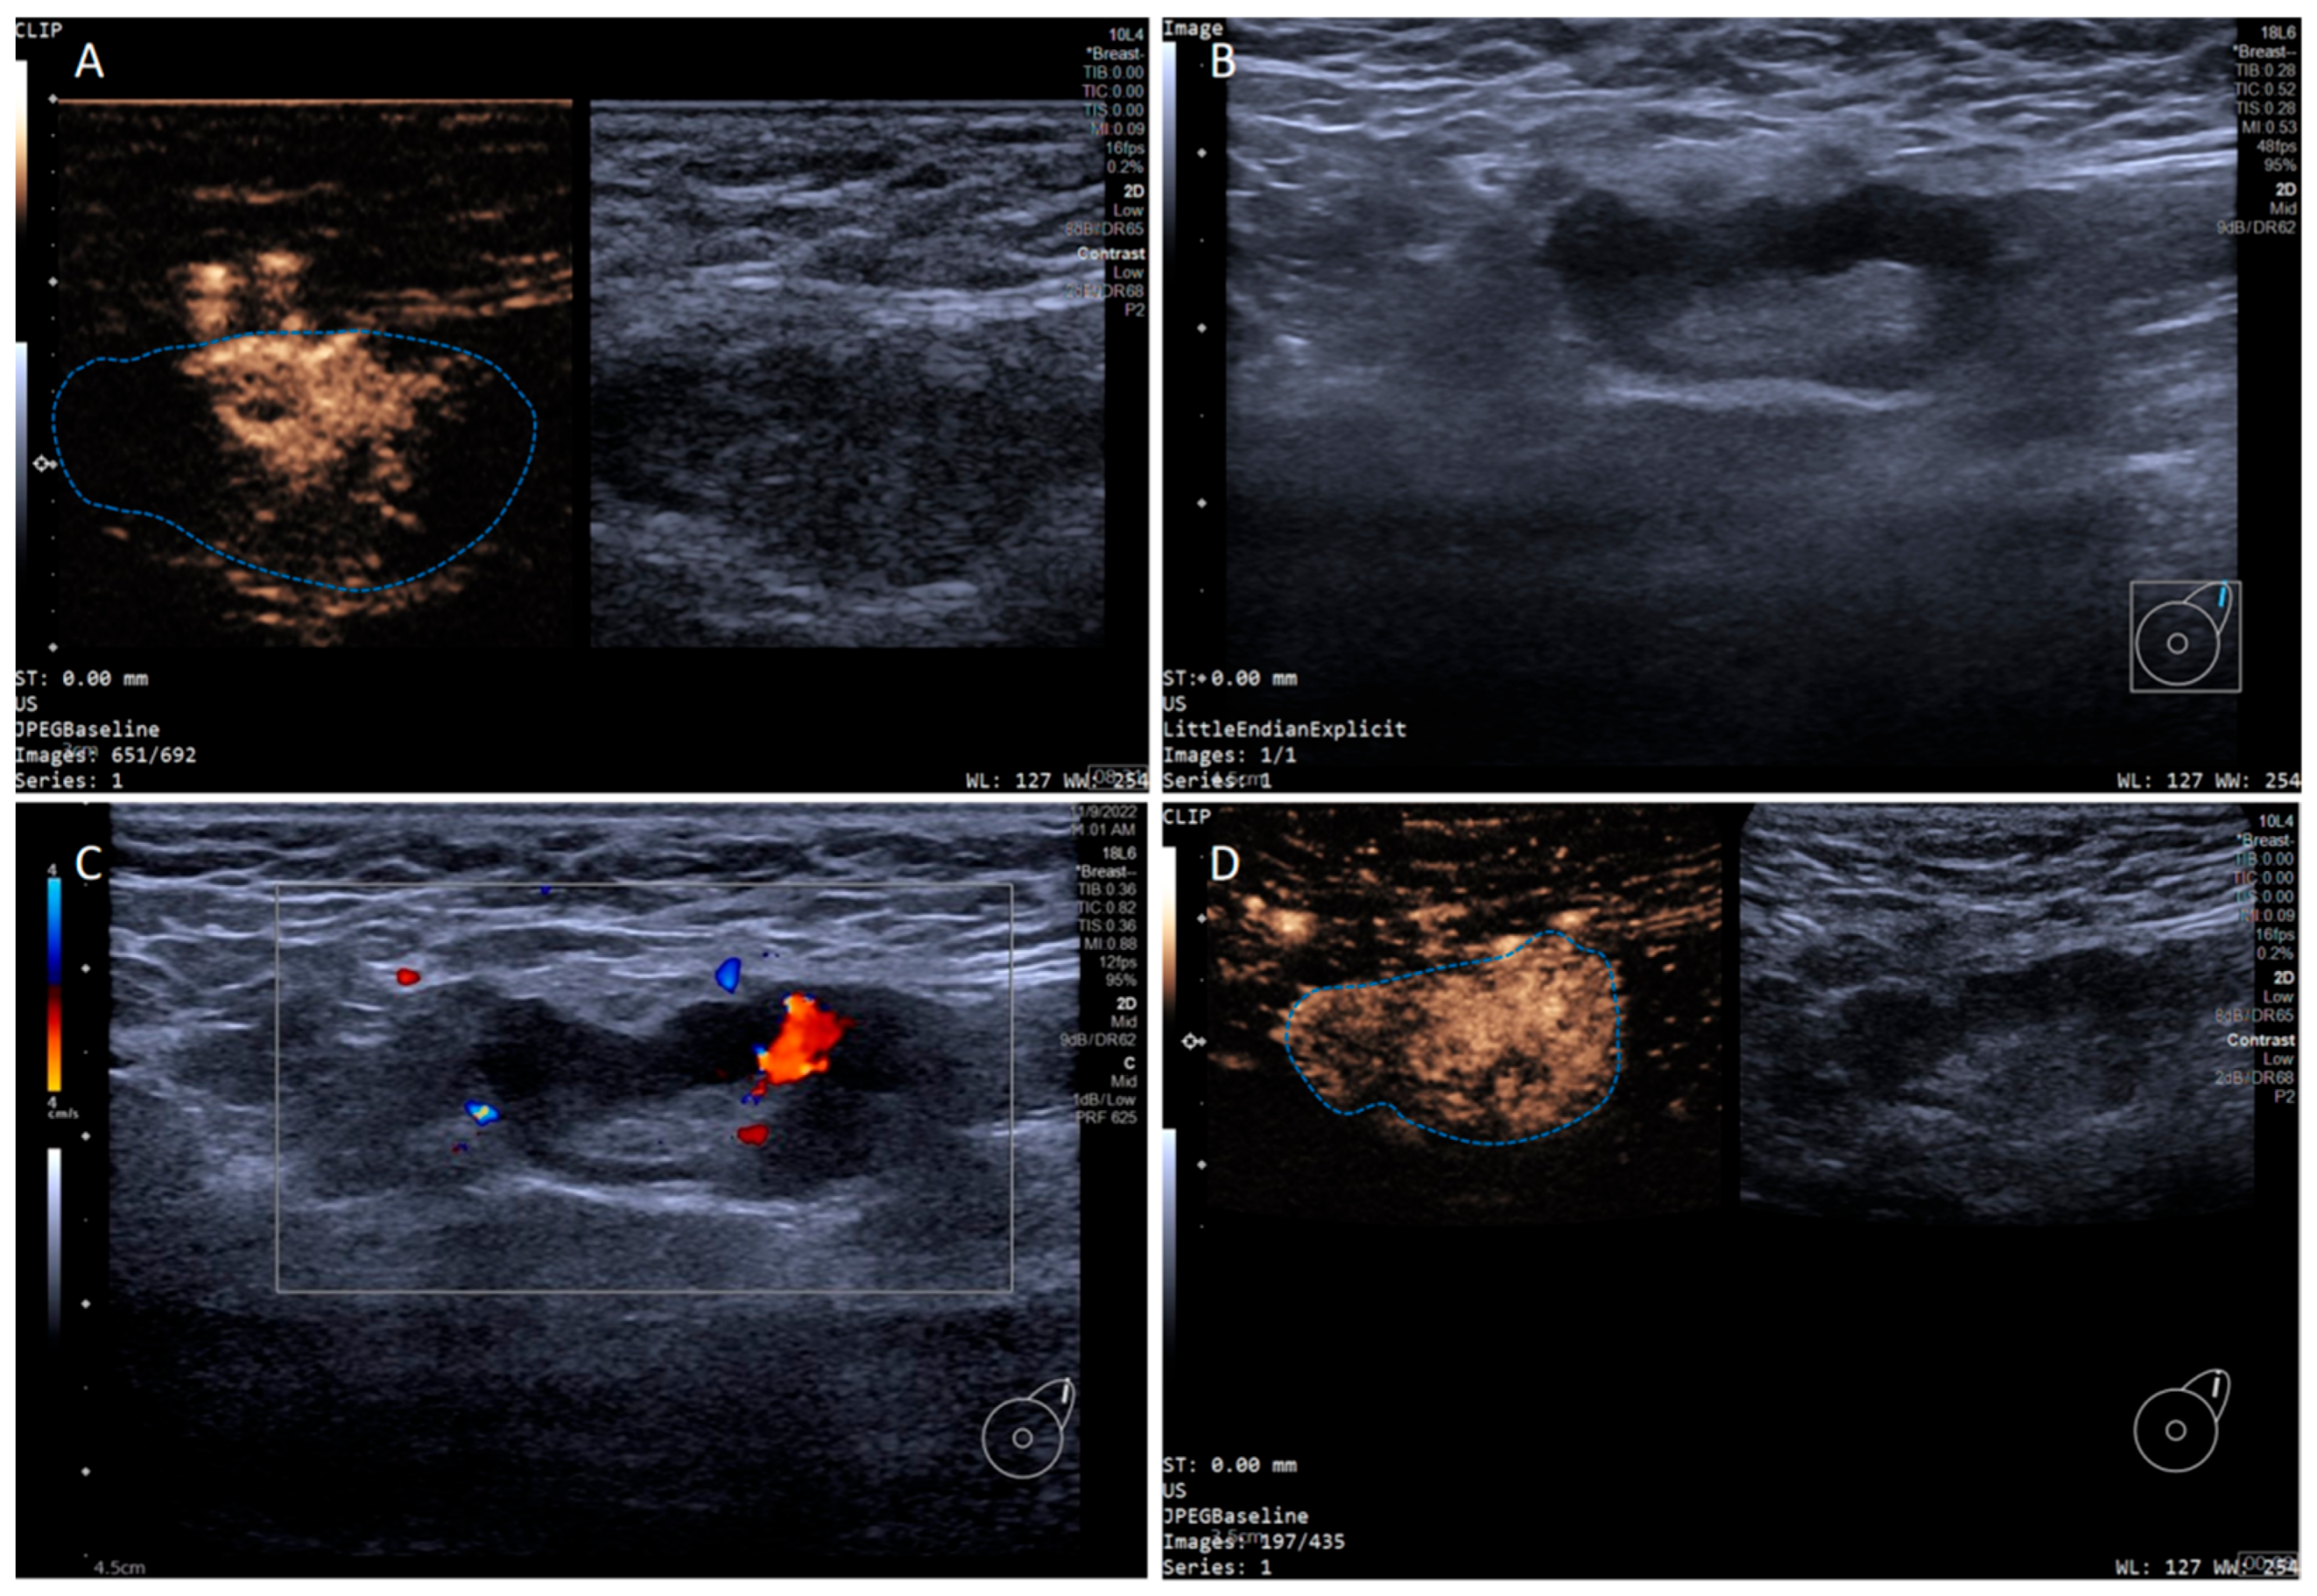

In addition, the SLN-IVCEUS enhancement patterns were divided into four types: type I showed homogeneous high enhancement; type II showed diffuse inhomogeneous high enhancement; type III showed no/low enhancement of the lymphatic hilus, homogeneous high enhancement of the cortex; type IV showed part of the cortical filling defect, low enhancement or high enhancement, the rest showed the performance of types I, II or III. And SLN-IVCEUS enhancement sequence was divided into three types based on the orders of bubbles entering the lymph nodes: centrifugal enhancement, centripetal enhancement, and diffuse enhancement. A malignant lymph node was diagnosed as long as one of the following conditions was met: (I) centripetal enhancement; (II) diffuse enhancement; (III) the enhancement mode of IVCEUS was type IV. SLN was diagnosed as malignant when PCEUS and/or IVCEUS diagnosed the SLN as malignant (Figure 2 and Figure 3).

Figure 3. Multimodal ultrasound imaging of pathologically confirmed metastatic sentinel lymph node. (A) Intradermal CEUS image (the enhancement pattern is type I, the blue dotted line delineates the contour of the SLN); (B) 2D US image; (C) CDFI image; (D) intravenous CEUS image (the enhancement pattern is II, the blue dotted line delineates the contour of the SLN).